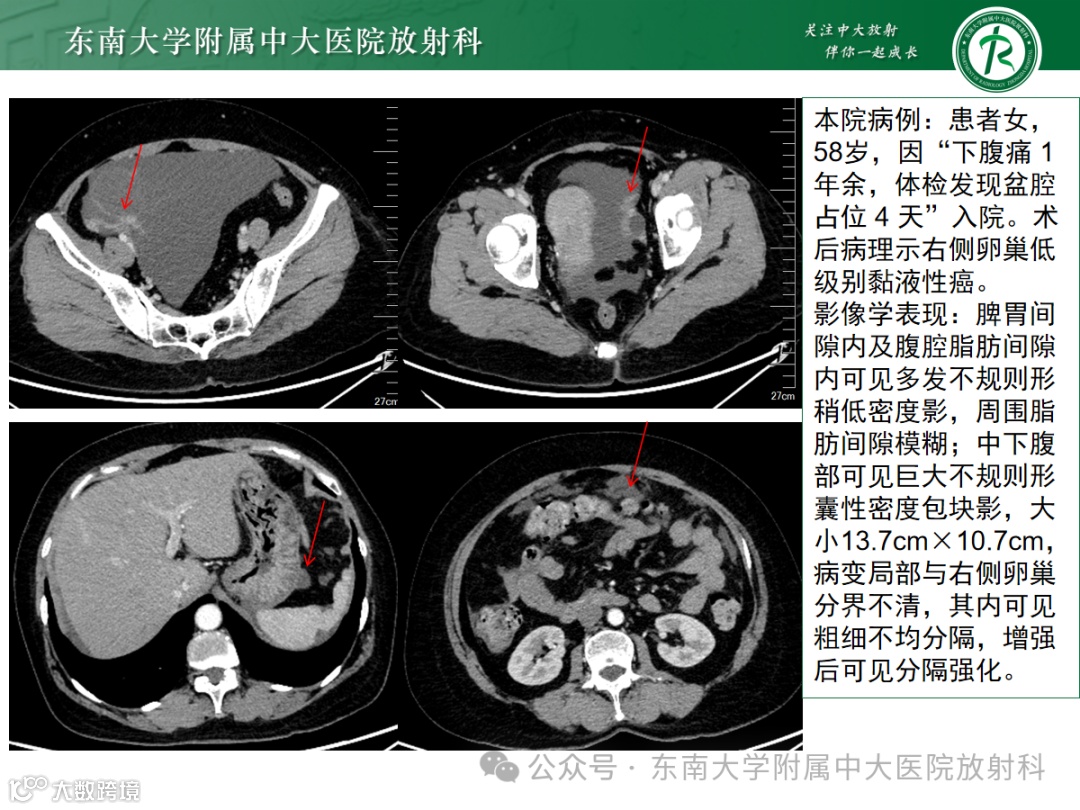

影像学表现